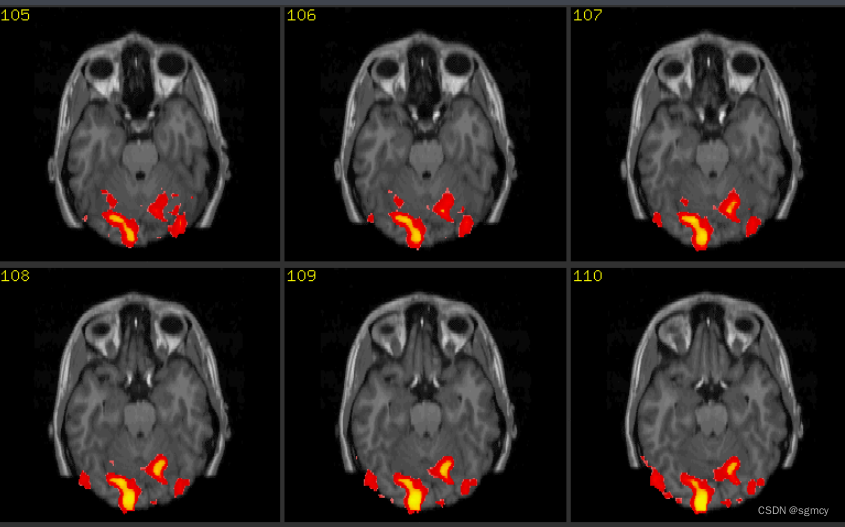

来源:CSND

第二种是非侵入式脑机接口,这就很好理解了,不会直接接触大脑皮层,仅通过头皮采集脑电信号。但以这种方式采集到的信号纯度不高,而且还会伴有大量的噪音。